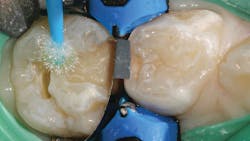

A selective-etch technique with 35% phosphoric acid is used to achieve the highest possible bond strengths.6,7 The etchant is washed and the tooth is dried without desiccating it. A universal bonding agent (Futurabond U, Voco) is rubbed onto the tooth surface for 20 seconds (figure 3), and thenThis is a modified snowplow technique, in which the flowable base layer is light cured in combination with placement of 4 mm of the restorative material.8,9 This allows the flowable to extrude up to the occlusal surface and down to the gingival margins, filling any voids.

The restorative material is warmed first in a Caps WarmerNano-ORMOCER materials provide clinicians with an excellent restorative option for pediatric patients that can appease concerned caregivers without disrupting current workflows. No doubt public scrutiny of our restorative materials will continue, whether their conclusions are legitimate or ill-informed. But we will also continue to see children with dental caries, so we would do well to add new materials to our armamentarium that can support good oral health outcomes and reassure caregivers of their safety.